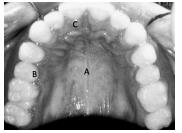

Considerando a imagem apresentada acima, julgue o item subsecutivo.

A letra A indica o palato duro.